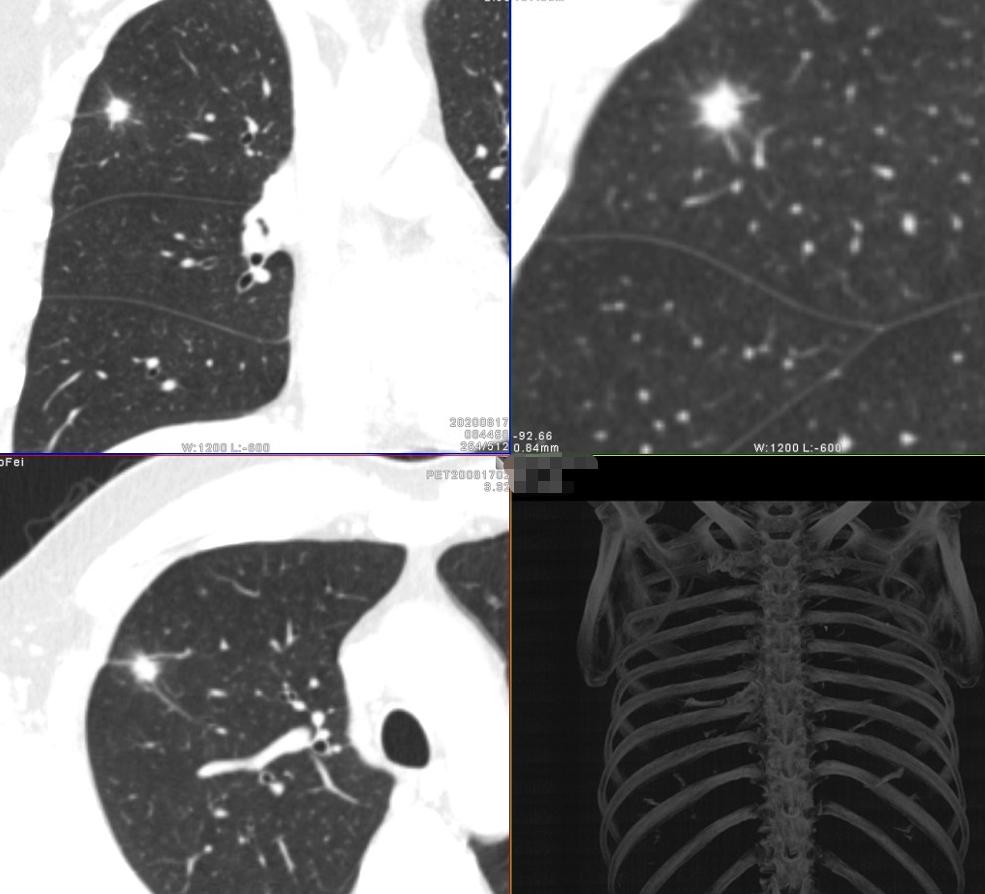

1:女性 47岁 体检发现右肺结节1周,预行手术,进行术前分期、评估。

薄层高分辨三维重组图片

妥妥的恶性征象,令人心惊胆寒

影像学检查特点:右肺上叶尖段实性结节,大小1.2cm×1.1cm×1.0cm,分叶毛刺、胸膜牵拉,最主要的是有两个大的引流血管汇聚,诊断为恶性病变还需要理由吗?不需要理由。这种征象哪个医生也不敢说一定是良性的。建议活检应该是最好的选择。